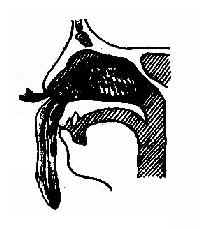

出血部位大多数和在鼻中隔前下部的易出血区(Little 区),其原因如下:①鼻中隔前下部有鼻腭动脉、筛前动脉、上唇动脉鼻中隔支及腭大动脉分支相互吻合,形成网状血管丛(图1-11)。②鼻中隔前下部粘膜甚薄,血管极易损伤,且由于这些血管与软骨关系紧密,破裂后不易收缩。③鼻中隔前下部极易因挖鼻而损伤,而且容易遭受空气刺激,使粘膜干燥、结痂,干痂脱落时易发生出血。若鼻中隔有偏曲或距状突,这种情况更为常见。儿童鼻出血几乎全部发生在鼻腔前部;青年人虽以鼻腔前部出血多见,但也有少数严重的出血发生在鼻腔后部。40岁以上的中老年人的鼻出血,常与高血压和动脉硬化有关,出血部位见于鼻腔后部,位于下鼻甲后端附近的鼻咽静脉丛(Woodrff’s plexus)为鼻后部出血的较常见部位。